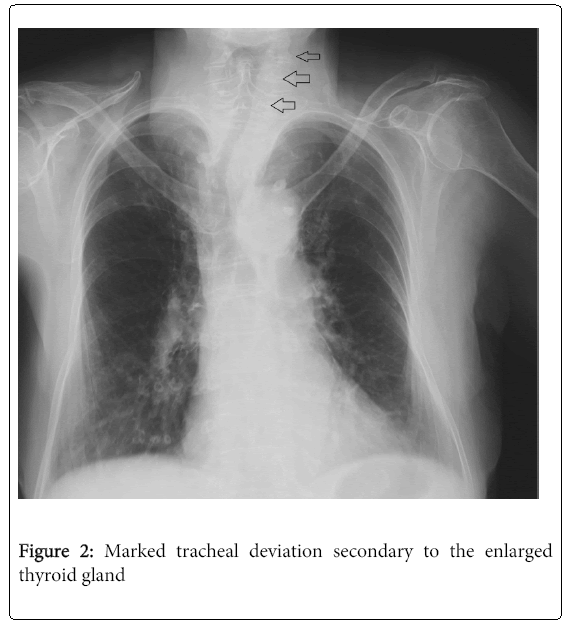

From omicsgroup.org

emergencymedicineMarkedtrachealdeviation Tracheal Deviation Neck Tracheal deviation is sometimes seen on preoperative chest radiographs. Web tracheal deviation is the displacement of the trachea from its normal central position due to various conditions, such as pneumothorax,. It can be a symptom of various conditions, such as pneumothorax,. Web tracheal deviation is a shift of the trachea to one side caused by abnormal pressure in the chest. Tracheal Deviation Neck.